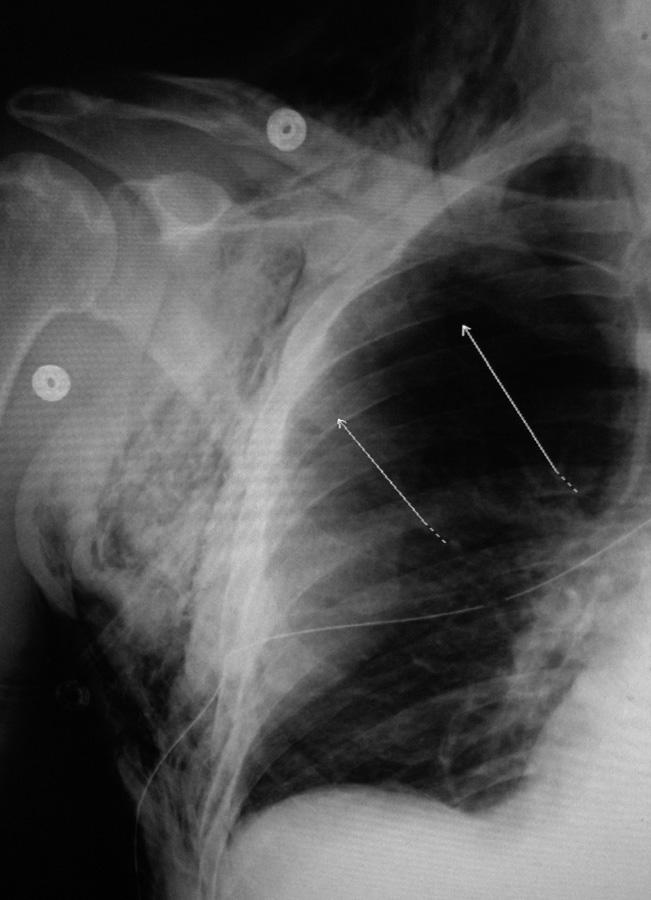

Neonate with a right tension pneumothorax. Note the tracheal deviation to the left.

Subcutaneous Emphysema and Pneumothorax